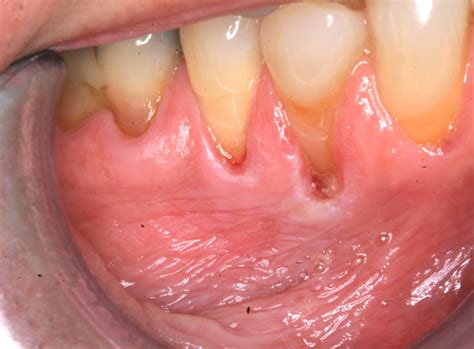

Spitting Tobacco Use Leads To Severe Gum Recession And Rot

Smoking Effects on Oral Health Severe Gum Recession and Tooth Decay in

PPT - Truth about Severe Gum Recession PowerPoint Presentation, free